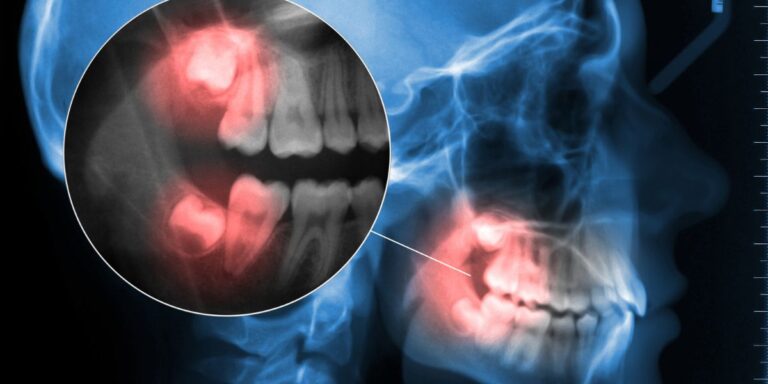

Cosa sono i denti del giudizio Si chiamano così perché normalmente erompono tra i 16…